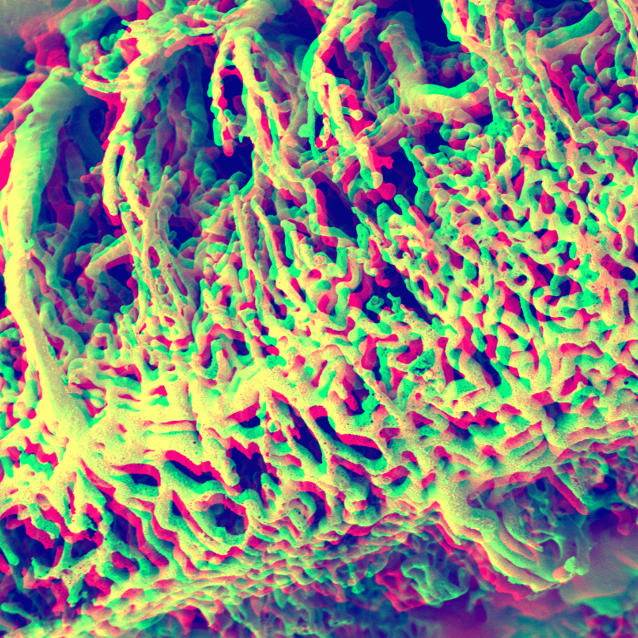

Pulmonary circulation

Anaglyphic 3D SEM image of microvascular corrosion cast  illustrates numerous alveolar baskets adjacent to the bronchial walls.